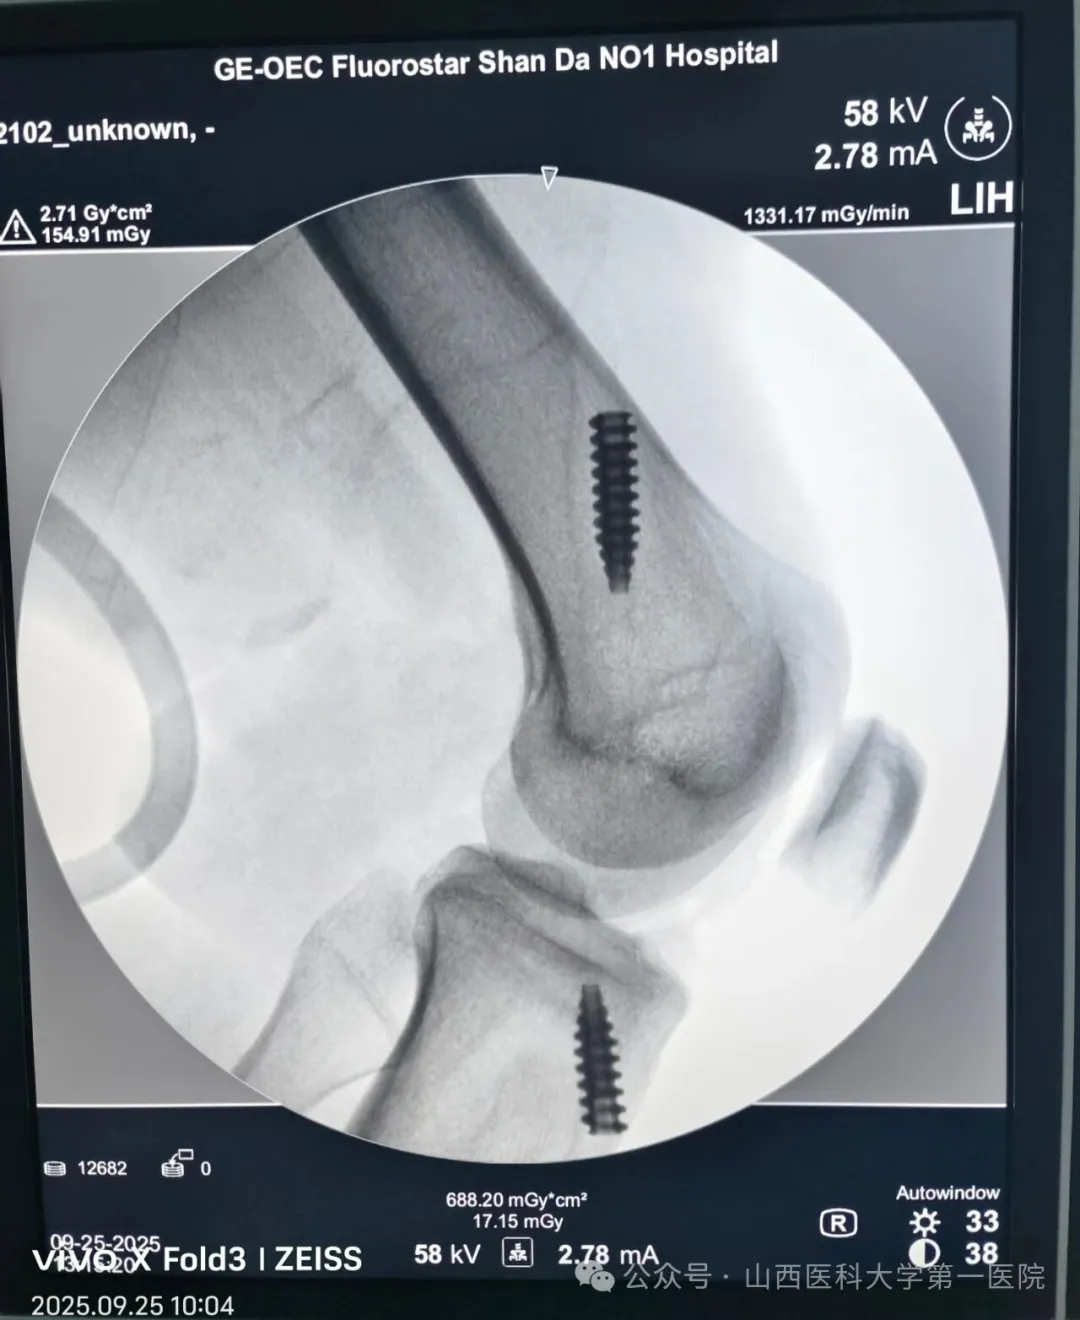

9 月 25 日 7 时 30 分,患者正式入住日间手术中心。在完成术前检查与麻醉评估后,手术团队迅速进入操作环节。据韩晓强主任医师介绍,此次手术采用的人工韧带强度约为自体韧带的 3.2 倍,不仅能更稳固地重建受损韧带,还能让患者在术后即刻启动康复锻炼,为肌肉与关节功能恢复抢占 “黄金时间”。历经 1 小时 40 分钟精细操作,手术顺利完成。